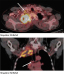

Pancoast-Tumoren sind eine rasch fortschreitende Sonderform des Bronchuskarzinoms. Sie wurden im Jahr 1932 durch Henry Pancoast als eigene Krankheitsentität erstbeschrieben. Seit damals hat sich die Behandlung von ehemals rein palliativen Konzepten zu kurativen multimodalen Therapieansätzen hin entwickelt. Durch aggressive Chemo-Radio-Induktionsprotokolle und eine kontinuierliche Weiterentwicklung der chirurgischen Techniken konnte die Prognose der Erkrankung erheblich verbessert werden. Der folgende Artikel soll eine kurze Zusammenfassung heutiger Behandlungskonzepte aus Sicht des Chirurgen geben.